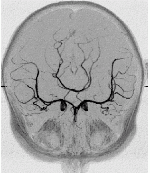

This example illustrates the process of grid generation starting from medical images. In this case a model of the circle of Willis was reconstructed from contrast-enhanced MRA images using a region growing algorithm.

First the anatomical 3D images are processed and segmented in order to label the voxels that belong to the desired arteries. This process is illustrated in the next two images where the maximum intensity projection (MIP) of the images before and after segmentation are shown.